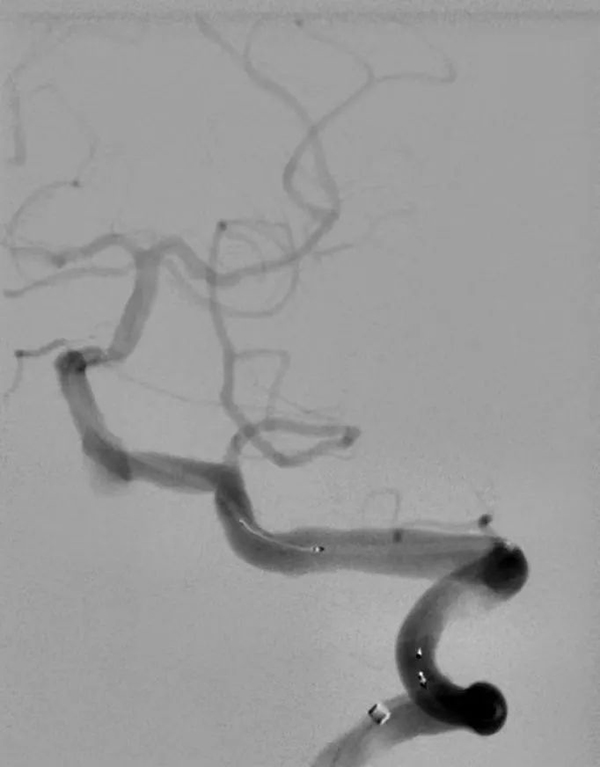

在市十院介入科团队、神经内科团队和医大二院神经外科团队共同努力下手术非常顺利,术中选用5F猪尾造影管开始进行主动脉弓造影和旋转造影见椎动脉V4段动脉瘤。选取工作角度,应用导丝超选至基底动脉,选用3.5*20mm pipeline II支架,定位释放。术后造影显示瘤体内血流灌注延迟缓慢。

支架置入中

支架置入后血流灌注延迟缓慢

这是市十院完成首例血流导向装置Pipeline Flex治疗颅内动脉瘤,标志着医院能够开展对患者损伤最小的脑动脉瘤微创治疗。与传统的支架辅助弹簧圈栓塞比较,Pipeline Flex置入因其简化手术步骤降低手术风险且愈合后不再复发的特点,在治疗此种复杂类型动脉瘤中具有明显优势;Pipeline Flex在全球应用已经超过10万例,其动脉瘤总体的1年完全闭塞率可以达到85.5%,总体并发症发生率为7.1%,成为了载瘤动脉邻近位置多发动脉瘤治疗的可靠选择。